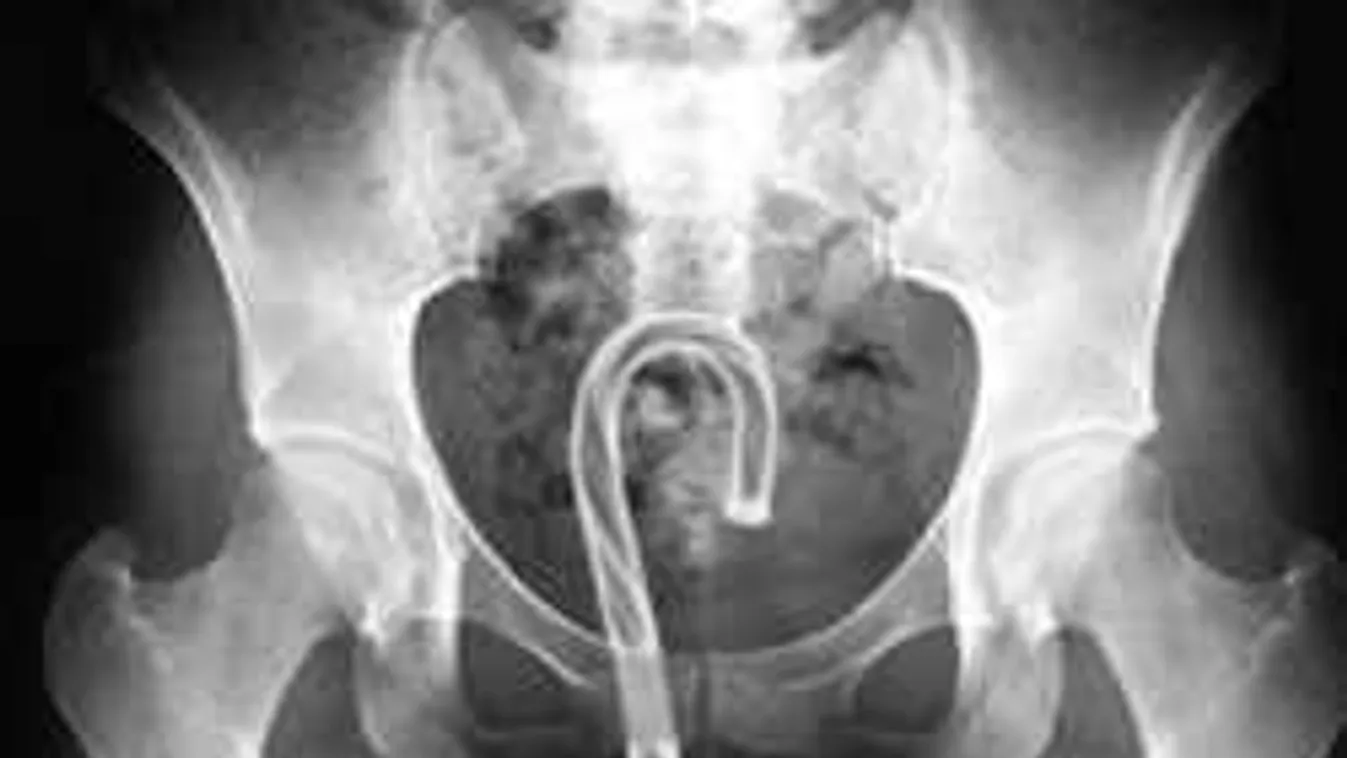

4. „Ne aggódj, drágám, tudok magamra vigyázni!” (pisztoly)

![]()